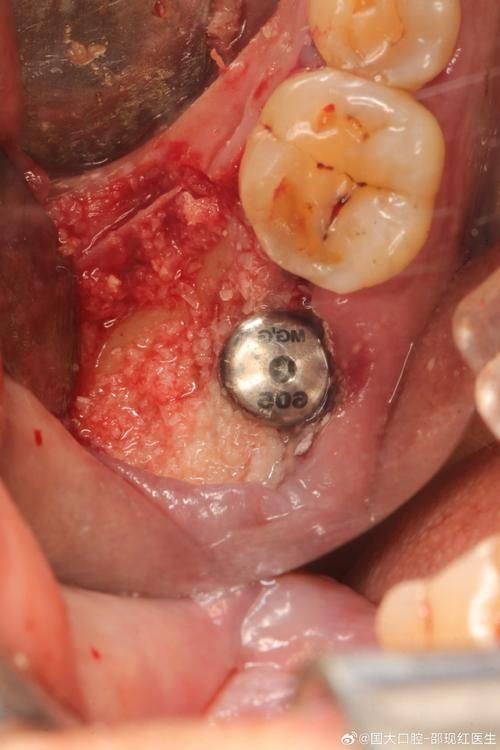

第二个擅长项目是即刻种植。即刻种植就是在拔牙后马上进行种植,这样可以节省治疗时间,减少患者的等待痛苦。高医生在即刻种植方面技术娴熟,他能够精细地把握拔牙和种植的时机,确保种植体能够顺利植入,并且与周围的组织理想融合。他就像是一位神奇的魔法师,能在短时间内为患者解决牙齿缺失的问题。

第三个擅长项目是即刻负重种植。即刻负重种植就是在种植后马上就可以承担一定的咀嚼压力,患者不用长时间等待牙齿愈合。高医生在这个项目上有自己独特的技术和方法,他会根据患者的具体情况,调整种植体的位置和角度,确保种植体能够承受住咀嚼压力,让患者能够尽快修复正常的饮食。

第三个技术优势是精细的操作。在进行种植手术等治疗时,高医生的操作非常精细。他会使用精良的设备和工具,严谨地定位种植体的位置和角度,确保种植的成效。他的精细操作就像一位非凡的狙击手,能够正确地命中目标,为患者带来更好的治疗成效。